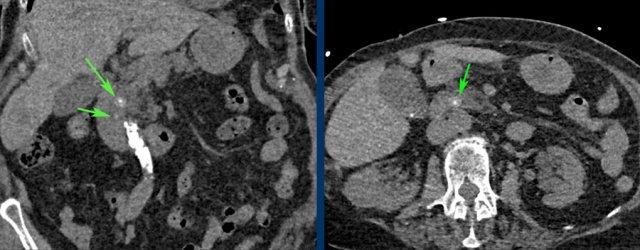

CT nghi ngờ bóc tách động mạch chủ. Phát hiện duy nhất có ý nghĩa là hai sỏi OMC, thấy rõ nhất trên chuỗi chụp không tiêm thuốc cản quang (mũi tên).